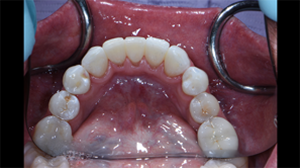

Fig. 11: Immediate post-operative lingual view again to show atraumatic and favorable tissue response and adaptation.

Fig. 12: Pre-operative (left) and post-operative (right) radiographs. The post-operative radiograph reveals the intimate adaptation and infinity edge margins that lend to the favorable tissue responses. Bioclear’s patented anatomic matrices enable predictable, atraumatic outcomes with subgingival contour changes unlike any other direct restorative methods.

Fig. 11 Fig. 12